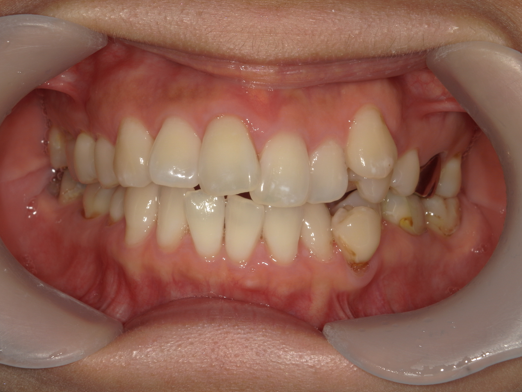

症例4:出っ歯が気になる

| 患者様データ | 10代 女性 |

| 来院主訴 | 出っ歯が気になる。 |

| 治療内容 | 出っ歯を治すために上下の小臼歯を4本抜歯し、表側ワイヤー矯正を開始しました。かみ合わせを整えるためにゴムかけを行いました。 |

| 概算治療費 | 約80万円 |

| 治療期間 | 2年6ヶ月 |

| 通院回数 | 30回 |